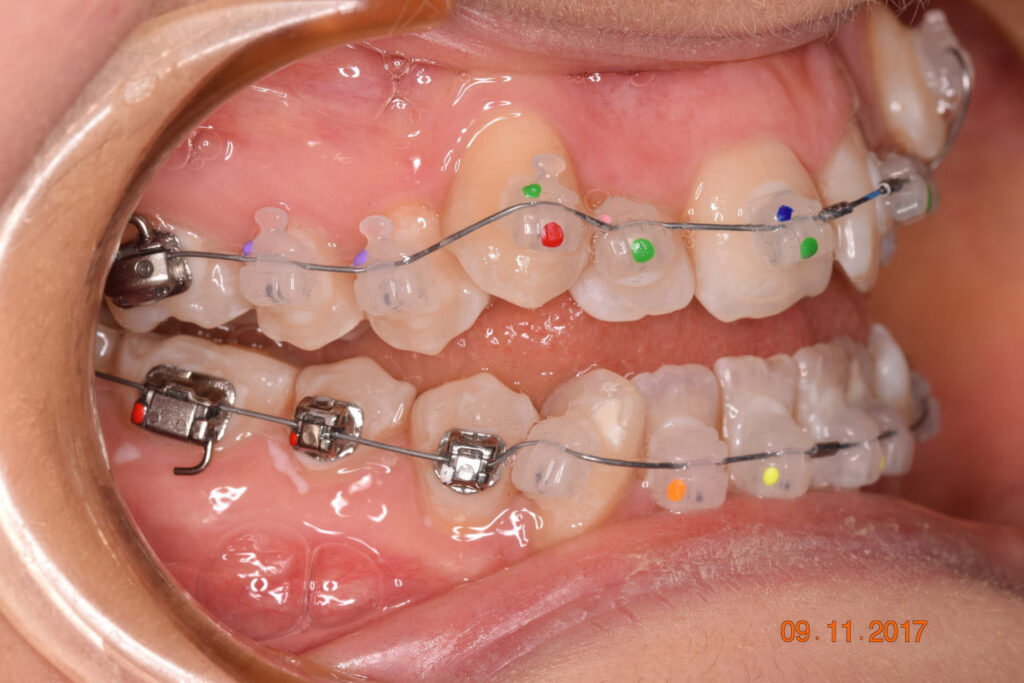

A 27-year-old female patient presented with class III malocclusion, 15 mm crowding in the upper arch, an anterior open bite, a lateral crossbite, and a total ABO score of 29. Her facial profile was straight with a retrusive maxilla, and the upper and lower incisors were retroclined. An extreme lack of midface support was also noted, and the constricted dental arches resulted in a poor smile width and dark buccal corridors. No myofunctional investigations were performed at the time, as they were initially considered unnecessary.

The treatment began in 2017. Given the patient’s preference for less visible brackets, Damon Clear brackets were selected. High torque upper cuspids and low torque upper incisors were chosen to offer the best torque control for upper arch development. For the lower arch, there were no alternative bracket configurations available. Bite turbos were applied to the upper second molars.